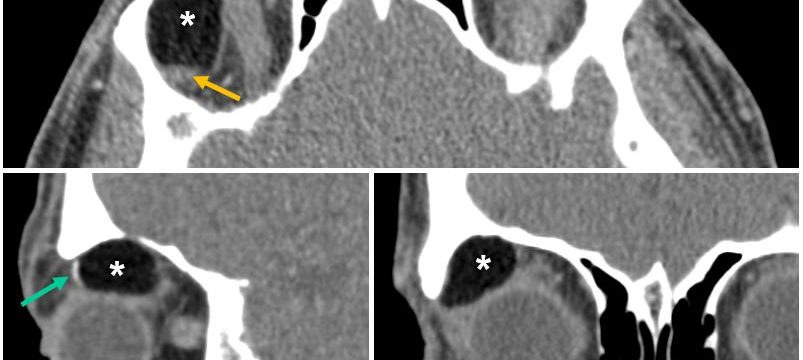

Mujer de 69 años de edad, con un cuadro de 7 meses de inestabilidad cefálica y de la marcha. Se realiza una RM craneal inicial, que es normal. Progresivamente, la síntomatología empeora, añadiéndose desorientación, alucinaciones, mioclonías y deterioro cognitivo. Se repite RM craneal por empeoramiento clínico progresivo.